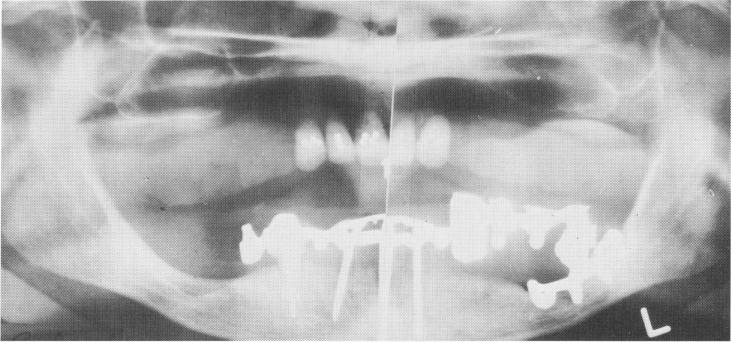

Fig. 13-49. A 5 1/2-year postoperative Panorex showing completed case. The left bicuspid had been removed and replaced with a unilateral subperiosteal implant.

Radiographs of the case show how each type of implant uniquely serves its particular purpose (Fig. 13-56) .

1 Left bicuspid removed & replaced with unilateral subperiosteal implant

2 Cuspid with complete horizontal fracture of root fitted with gold post

3 Ventplant tapped in edentulous bicuspid region behind cuspid post